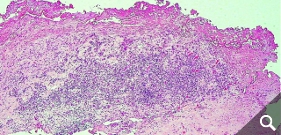

Skin tests (epicutaneous tests) do not show a clear correlation to the reaction of a joint to the implant, so that even skin testing for a metal or cement allergy cannot give a 100% indication. Therefore, in case of doubt, it is necessary to perform a tissue biopsy from the affected joint to provide the appropriate level of certainty. In the case of an allergy, lymphocyte infiltrates are frequently found in these tissues.

Beschichtete KnietotalendoprotheseDiffuse Lymphozyteninfiltration in der GelenkkapselOsteolyse um einen Prothesenschaft (Pfeile)